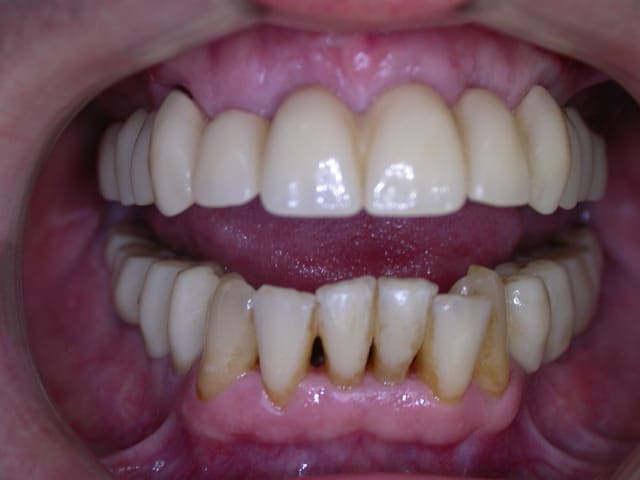

21 jours post-op

> 21 jours post-op

>

> Pp

comme quoi , finalement, même si nous ne sommes pas d'accord sur la façon d'y arriver, seul le résultat compte.

le patient est content.